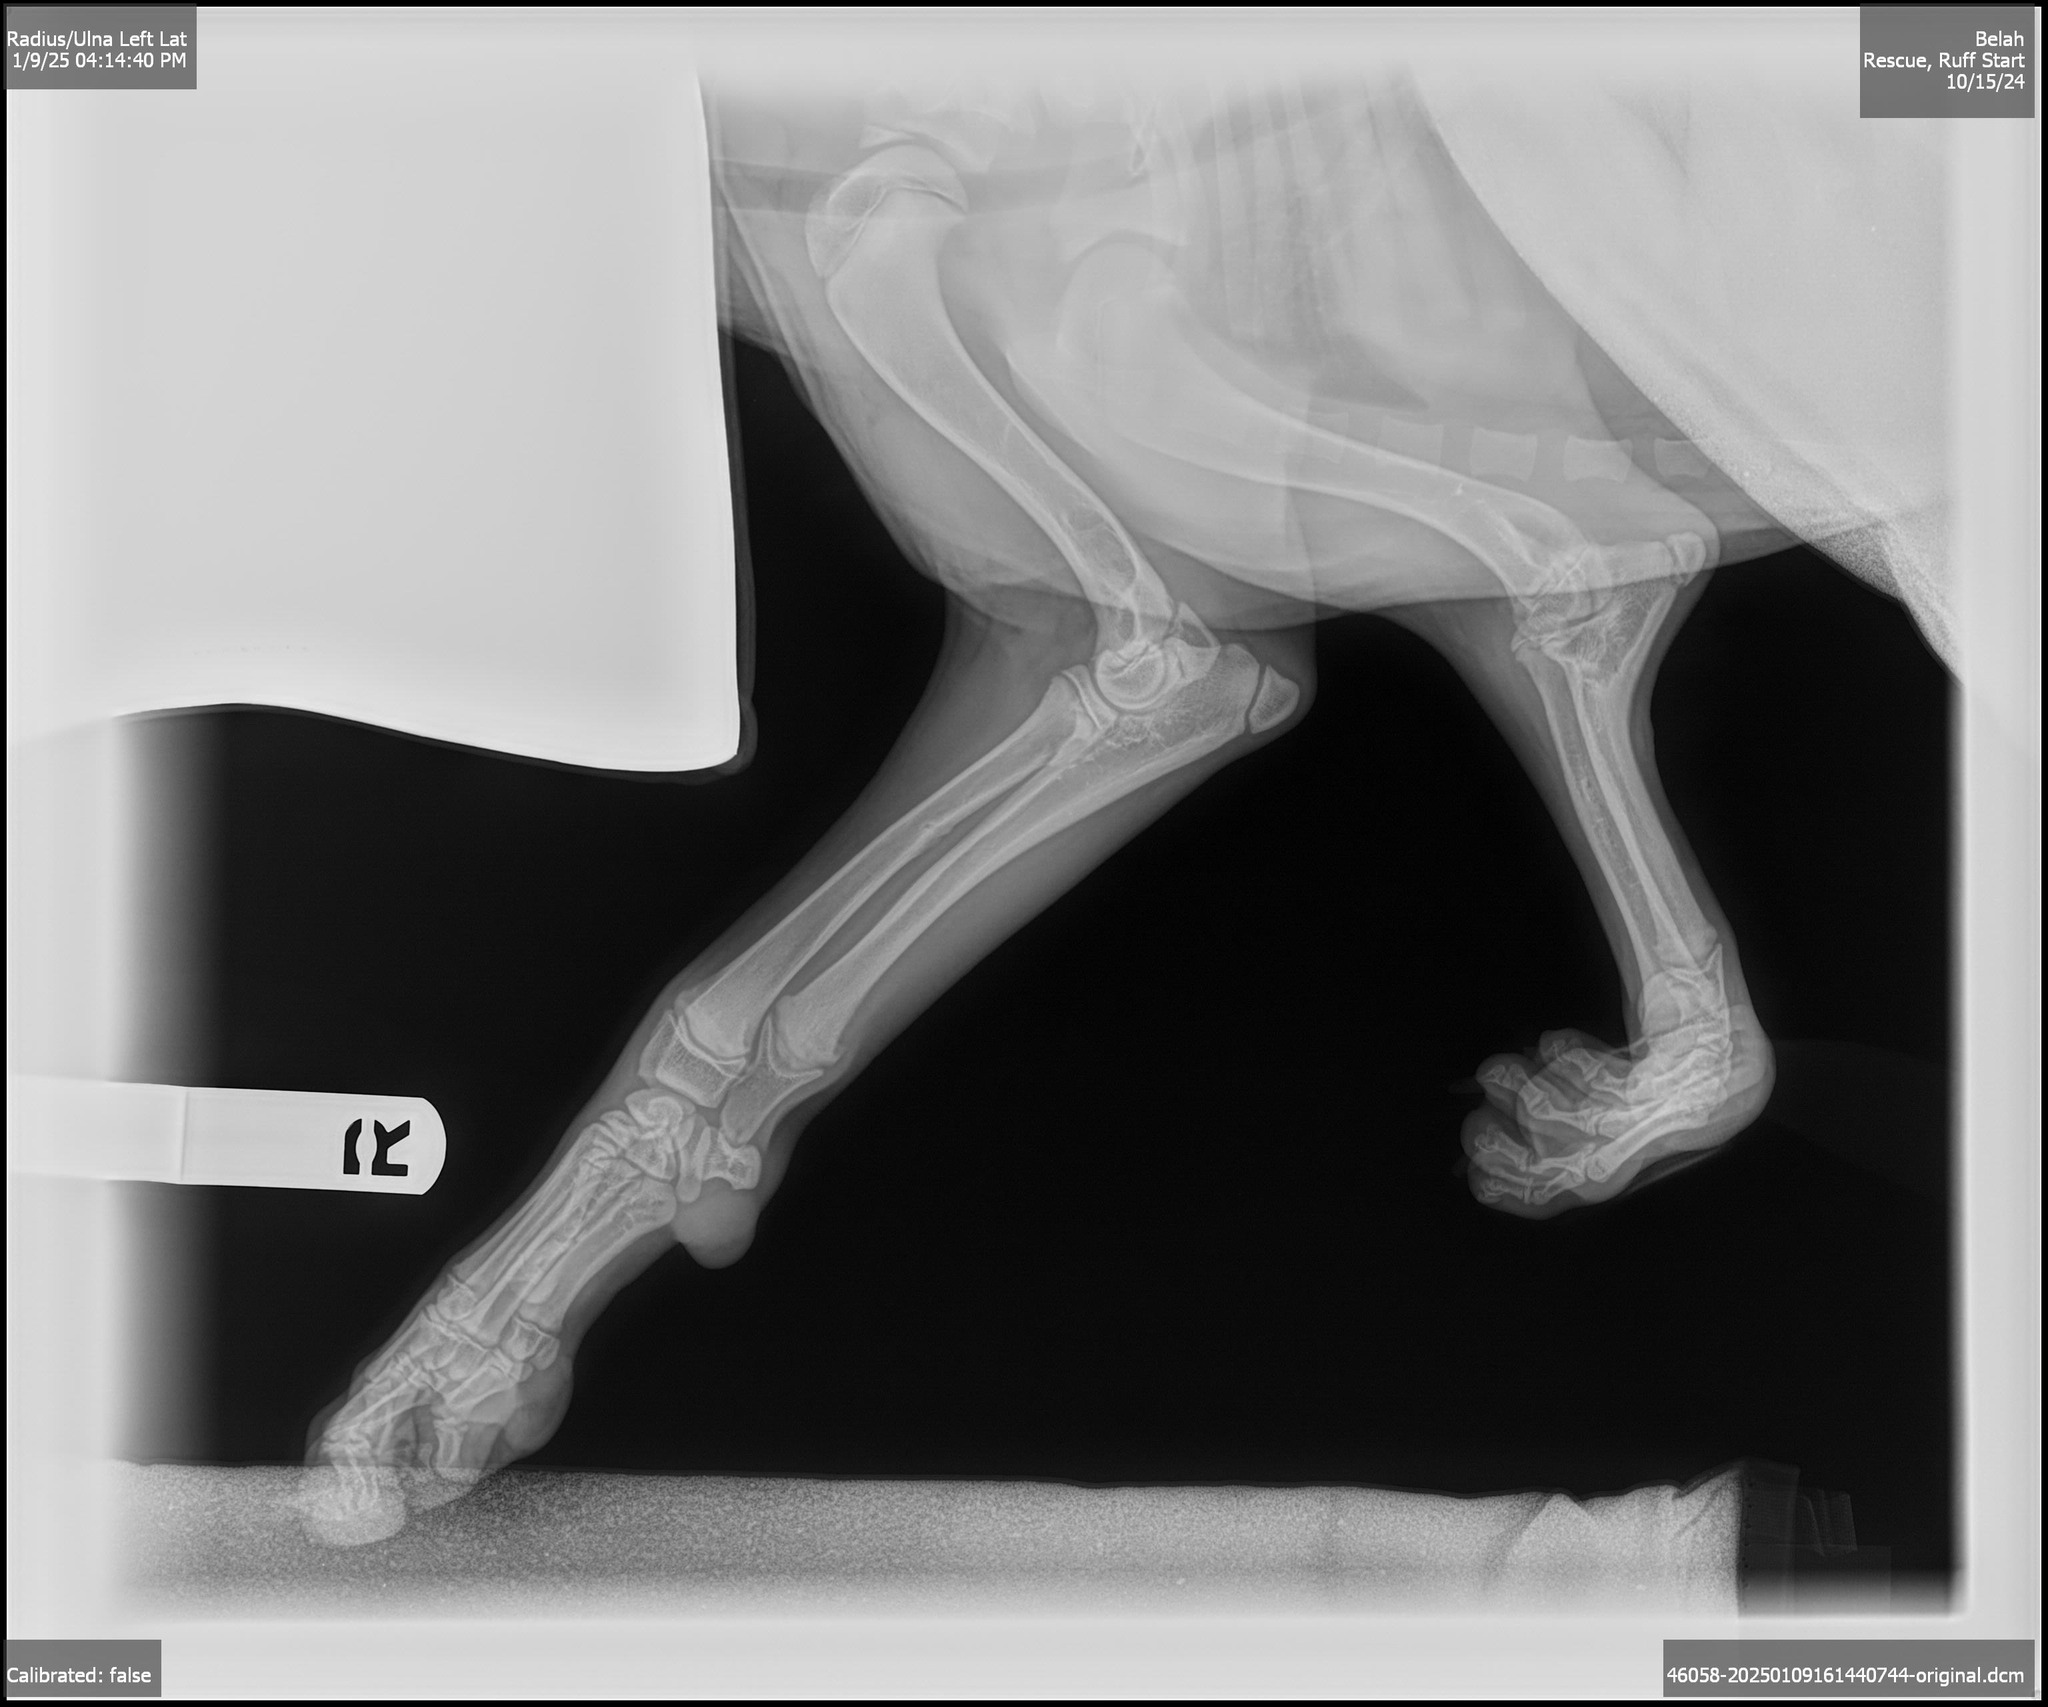

we learned that she has severe angular limb deformity in her left front leg and carpal hyperextension in her right front leg. Likely caused by birth defects or a past injury, her condition isn’t painful, but it does cause some instability.